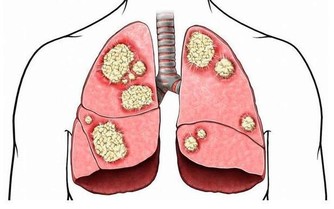

肺炎是可以治癒的,但根據不同的原因和病情輕重,治癒的時間和方法均不相同。比如輕症肺炎患者,通常在1、2週時間內得到治愈,而重症患者則需要更長的時間。

需要注意的是,對於本身患有基礎病的中老年患者來說,若出現嚴重的肺炎,可能會增加死亡的風險。